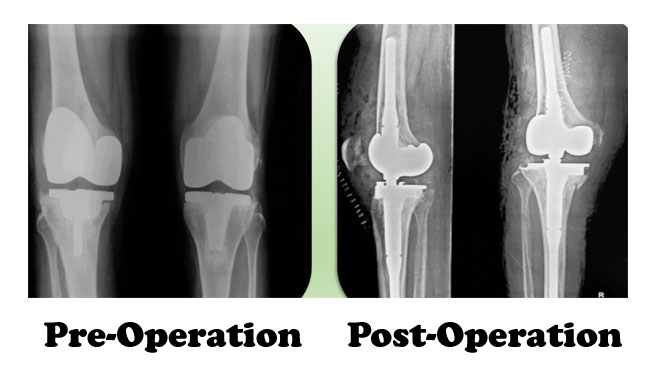

A knee revision is the replacement of prosthetic implants in a person who previously had a total knee replacement. In this surgery, known as a "reoperation," an original prosthesis is removed and a new prosthesis put in place.

Some knee revisions may require the replacement of only one implant, while others require a complete exchange of all the prostheses that were implanted during the original knee replacement surgery (known as "revision total knee replacement").